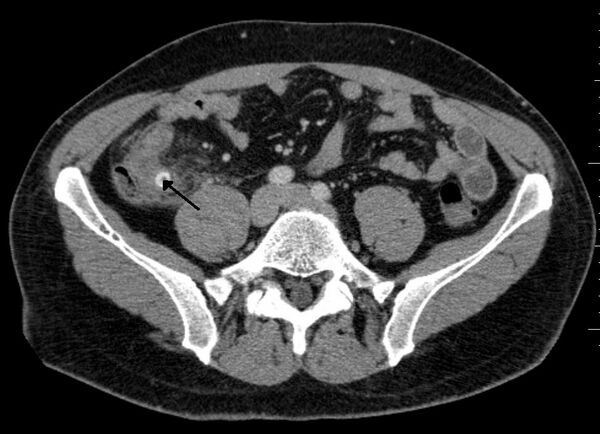

- Экспериментальные данные свидетельствуют о том, что острый аппендицит, по-видимому, возникает в результате обтурации (закупоривания) просвета червеобразного отростка[7][8]. Обтурация приводит к переполнению просвета отростка дистальнее уровня обтурации слизистым секретом. Диаметр отростка возрастает с 4-6 мм в норме до 17-18 и более миллиметров, он становится напряжённым. Нарастающее внутрипросветное давление в течение нескольких часов приводит к сдавлению внутриорганных вен, нарушению венозного и лимфатического оттока, отёку стенки органа и пропотеванию транссудата в его просвет с дальнейшим увеличением внутрипросветного давления («порочный круг»), что приводит к острому воспалению и некрозу (омертвению), прежде всего в зоне давления инородного тела («декубитальная язва», «пролежень», «флегмонозно-язвенный аппендицит»). Иногда копролиты можно обнаружить в просвете червеобразного отростка при остром катаральном или хроническом аппендиците. Почему они не приводят к деструкции органа и как долго находятся в его просвете, пока не ясно.

Ультразвуковое исследование — дилятация просвета (диаметр более 6 мм), отсутствие перистальтики, иногда может лоцироваться копролит. Ультразвуковое исследование должно быть первым инструментальным обследованием при подозрении на аппендицит. Обнаруживаются наполненная жидкостью, несжимаемая трубчатая конструкция с диаметром, превышающим 6 мм, аппендиколит, околоаппендикулярная перицекальная жидкость.

Компьютерная томография информативна при наличии спирального томографа, когда выявляется обтурация червеобразного отростка, расширение его просвета, утолщение стенки (> 1 мм), признаки свободной жидкости (воспалительного выпота) в брюшной полости.